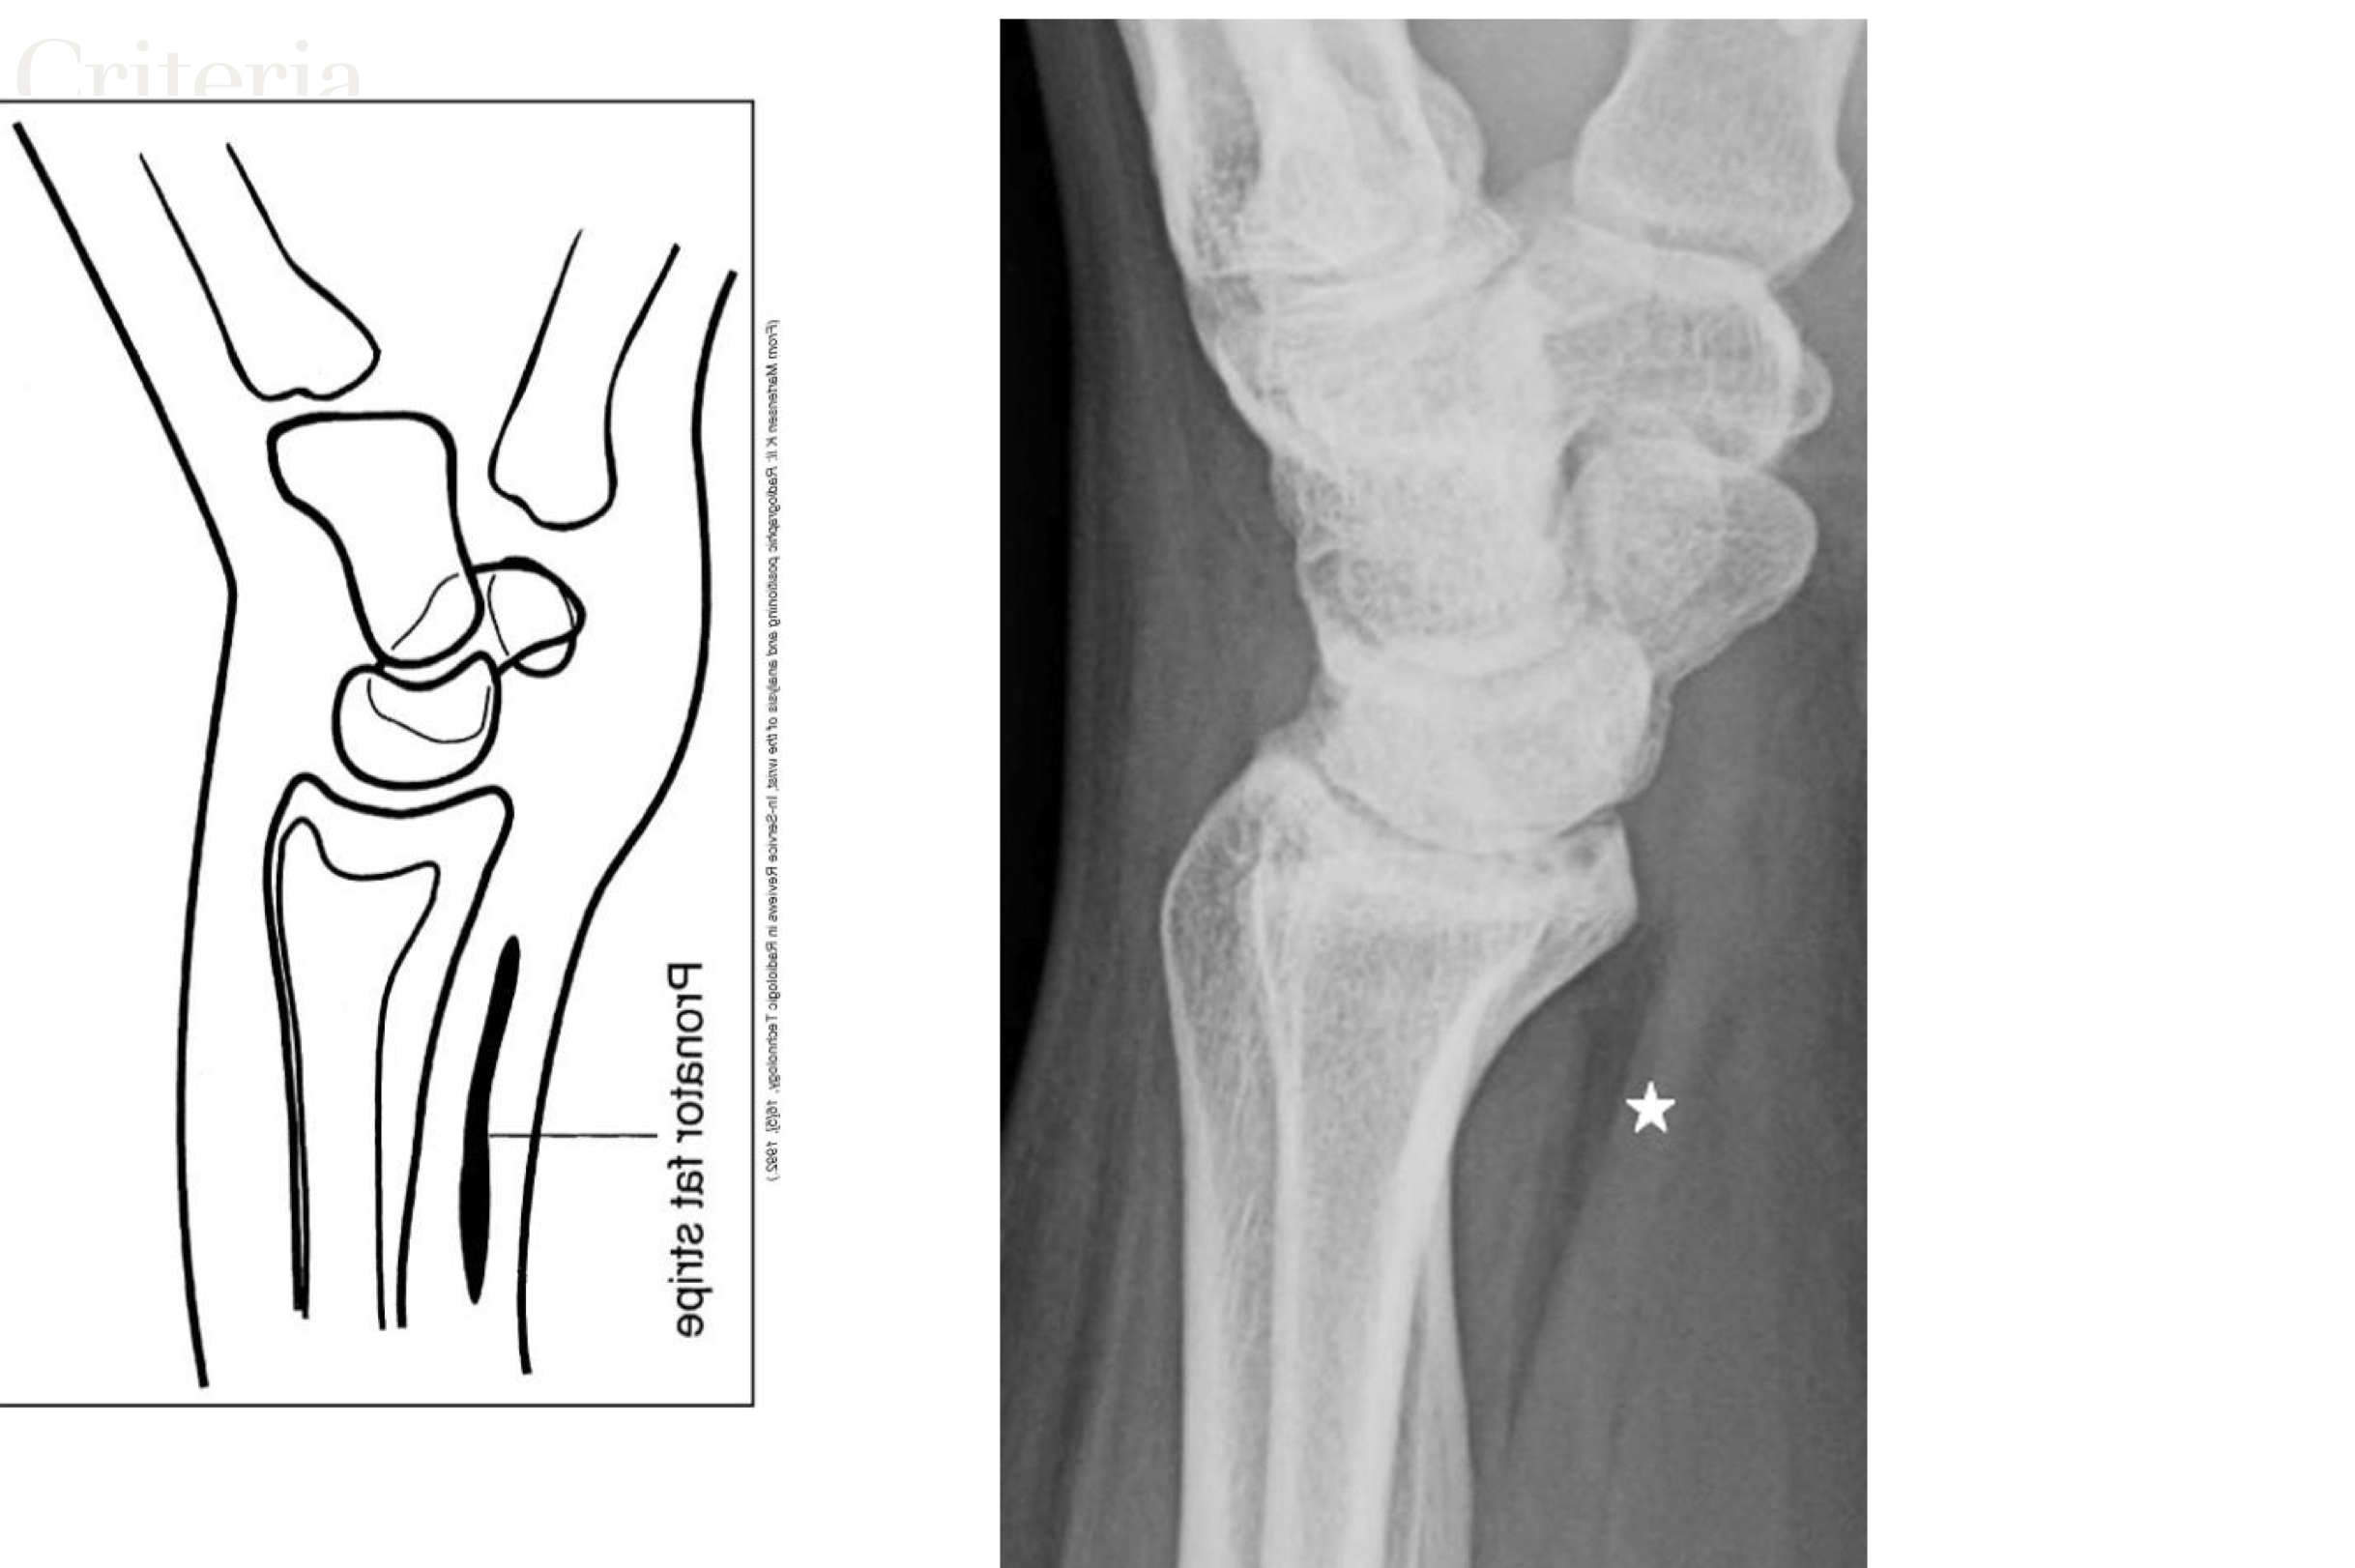

scaphoid fat stripe

looks black, sign of fracture or dislocation. On PA and oblique wrist projections

• Exposure factors demonstrate the pronator fat stripe

pronator fat stripe

on prone/anterior side. Always present